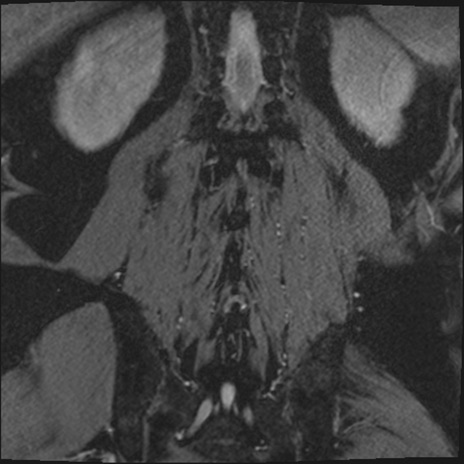

【整形】TIPS症例2 腰椎MRI 3D(冠状断像)

【症例】70歳代男性

【主訴】左下肢痛

【現病歴】2週間前くらいから腰痛、左下肢痛あり。左臀部から大腿、下腿外側のしびれが常時ある。歩行とともに同部位の痛みあり。

【身体所見】Lasegue70-/60+、Bragard-/±、PTR ±/±、ATR -/-、IP 5/5、TA 5/4、TS 5/5、EHL 右第1足趾なし/3、FHL 5/5、hypersthesia(-)、足背動脈触知良好

異常所見と診断は?